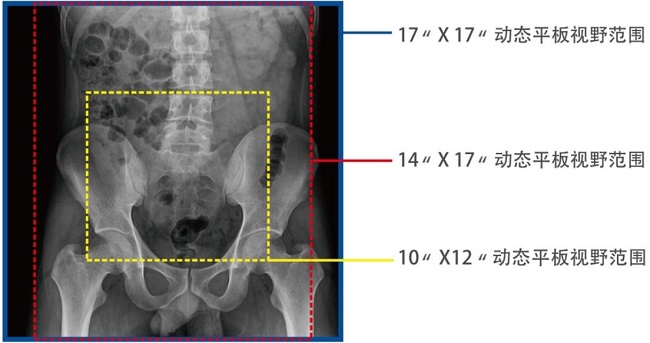

17*17英寸的超高清像素动态平板探测器,更大的视野范围,能对胸部腹部等部位实现大范围全覆盖,动静态之间无感切换。透视检查无须对患者重新定位便可观察到足够大的人体器官组织,避免漏诊误诊。

大尺寸动态平板技术,覆盖检查面积范围广,轻松实现胃十二指肠等大面积造影,无需移动即可观看整个动态过程,避免噪点对图像的影响。